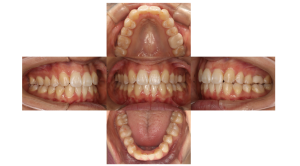

歯の凹凸が気になるお悩みです。

凸凹がなくなりキレイに歯が並びました。

| 主訴 | 【主訴】歯の凹凸を治したい、八重歯が気になる【診断・症状】叢生 |

| 治療費用 | 検査・診断:税込38,500円/裏側矯正治療(リンガル矯正):税込1,397,000円 |

| 治療期間 | 約1年6ヶ月(通院回数16回) |

| 抜歯 | 上下左右2番 |

| 矯正の装置 | 裏側矯正(舌側矯正) |

| 副作用、リスク | 歯肉退縮,歯根吸収,疼痛,咬合の違和感,装置の違和感,虫歯,歯肉炎 |